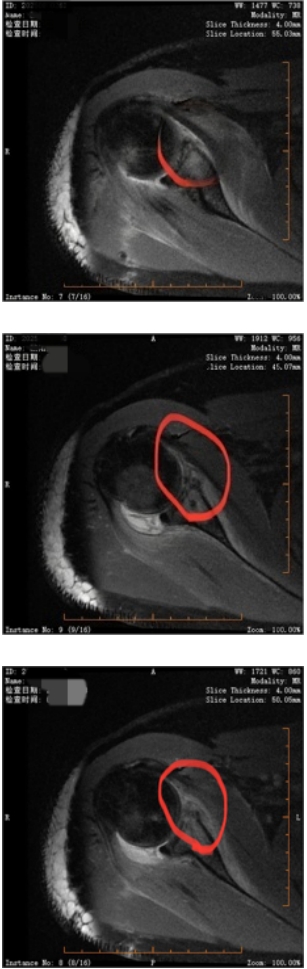

完善术前准备后,医生在全麻下为其实施关节镜微创手术,仅通过4个5毫米左右的小孔,便完成了Bankart修复和冈下肌填塞。

【术中影像资料】

术后第二天,小欧就在支具保护下开始康复锻炼,目前已顺利康复出院。

【术后复查MRI:修复后的孟唇组织】